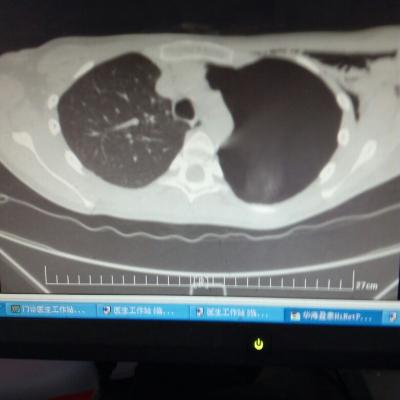

主诉:反酸、烧心5年,加重1年。 病史:患者5年前饮酒出现反酸烧心,并嗳气症状,剑突下烧灼感,饮酒及平卧后加重,无恶心呕吐,无腹痛腹泻,无吞咽困难,服用“达喜”后症状可缓解,易反复发作。3天前我科门诊示:胃镜反流性食管炎(LA-B),现为进一步诊治入院。

1.胃食管反流病 1.1反流性食管炎LA-B 2.食管裂孔疝 处理:患者诊断明确,行腹腔镜下食管裂孔疝修补术+胃底折叠术。

患者术后一周出院,反酸、烧心、嗳气症状明显缓解,无吞咽不畅等症状。 讨论:对于诊断有食管裂孔疝病人的胃食管反流病,且用药有一定疗效,建议行手术治疗,行腹腔镜下食管裂孔疝修补术,修补了膈裂孔,同时行胃底折叠术,加紧了贲门括约肌压力,共同形成抗“反流瓣”。